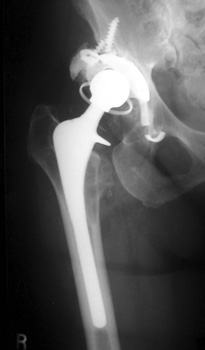

Broken, frayed, and disintegrating cerclage cables

Side plate placed for periprosthetic fracture, now broken with loss of reduction of femur fracture

6/97

11/02